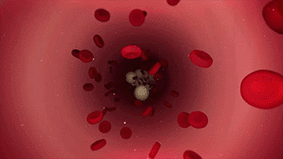

钇90是一种放射性核素,可以发射出纯β射线。钇90微球简单来说,就是含有放射性钇90物质的树脂微球,它非常小,直径仅有20-60微米,大约为人类头发丝直径的1/2。

钇90树脂微球它的治疗原理,就是通过一次微创介入手术,把数百万个钇90微球注射至滋养肝脏肿瘤的动脉血管,微球随血液进入肿瘤内部,让钇90释放的β射线近距离杀死肿瘤细胞。

由于β射线平均穿透距离仅为2.5毫米,减少了对正常肝脏组织和毗邻器官损伤,而且肝动脉的血流量高,大部分放射性物质均由肝肿瘤吸收,正常细胞接收极少,这种治疗方式更直接、更精准,而且最大程度避免了传统化疗放疗方式“杀敌一千,自损八百”带来的损伤。